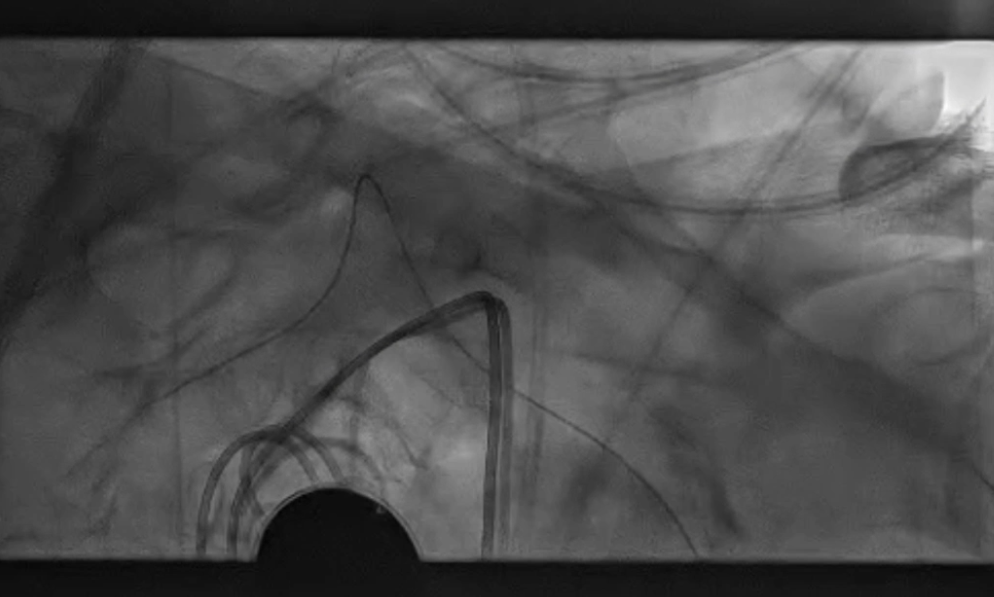

主动脉弓上造影显示无名动脉起始支架内重度狭窄,右椎动脉显影延迟,解除无名动脉支架内狭窄,恢复血流通畅,同时保障脑保护,降低并发症风险。

无名动脉起始支架内重度狭窄右椎动脉显影延迟

导丝与导管操作:超滑导丝配合多用途导管选入无名动脉,调整角度进入右锁骨下动脉;因主动脉弓扭曲严重,更换支撑导管通过病变段并造影证实

超选入无名动脉

无名动脉起始支架内

重度狭窄